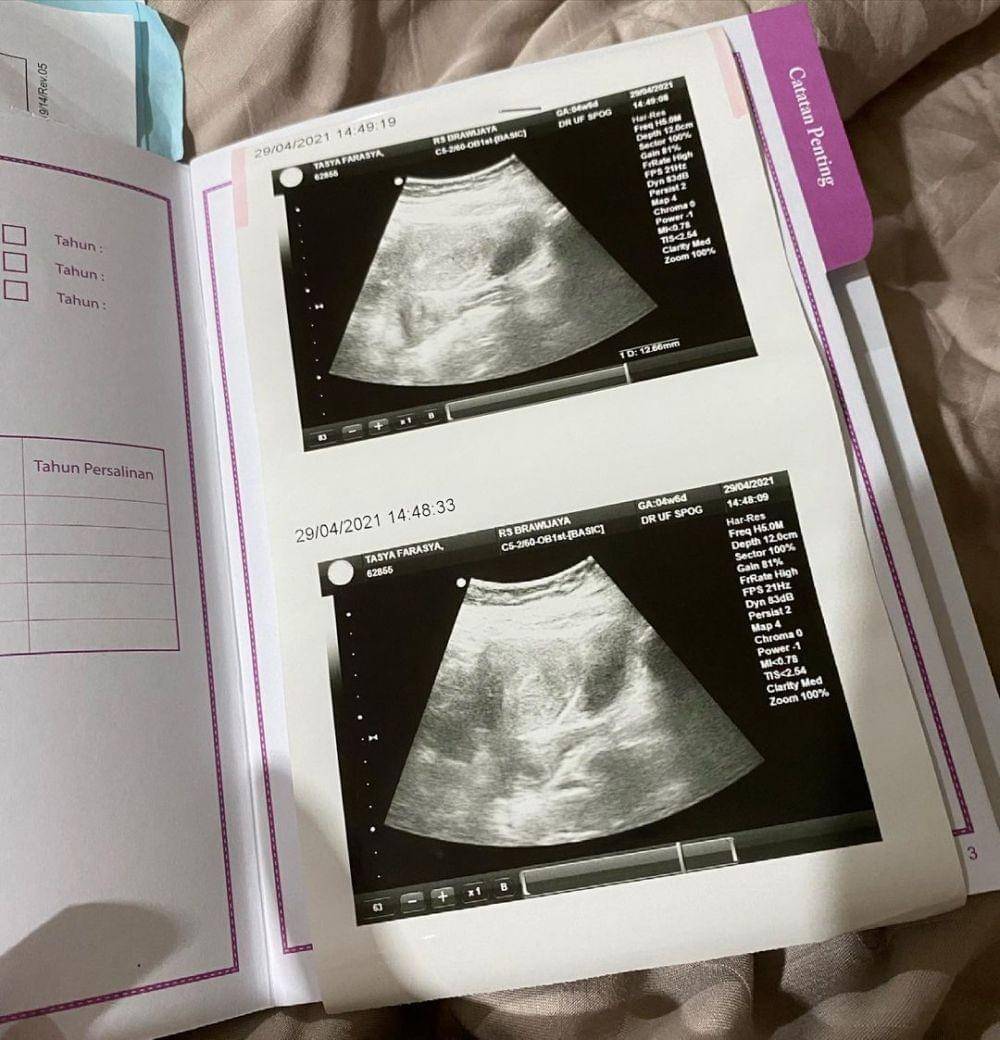

Tak hanya menuliskan kalimat duka, Tasya juga mengunggah sebuah foto USG calon buah hatinya yang diambil pada 29 April 2021. Dari foto USG tersebut, tertulis bahwa usia kehamilan Tasya saat itu adalah empat minggu enam hari. Sementara itu, pada foto selanjutnya, Tasya mengunggah foto dirinya yang sedang bersandar di bahu sang Suami.